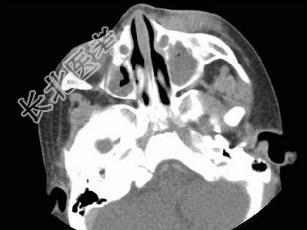

- 多项选择题女,2岁, 左侧眼睑肿胀发热,CT检查如图所示, 正确的描述或诊断是 ( )

A、左侧鼻骨外侧旁见软组织块影

B、其内密度不均,可见低密度影

C、左侧鼻泪管囊肿

D、鼻泪管脓肿

E、混合瘤